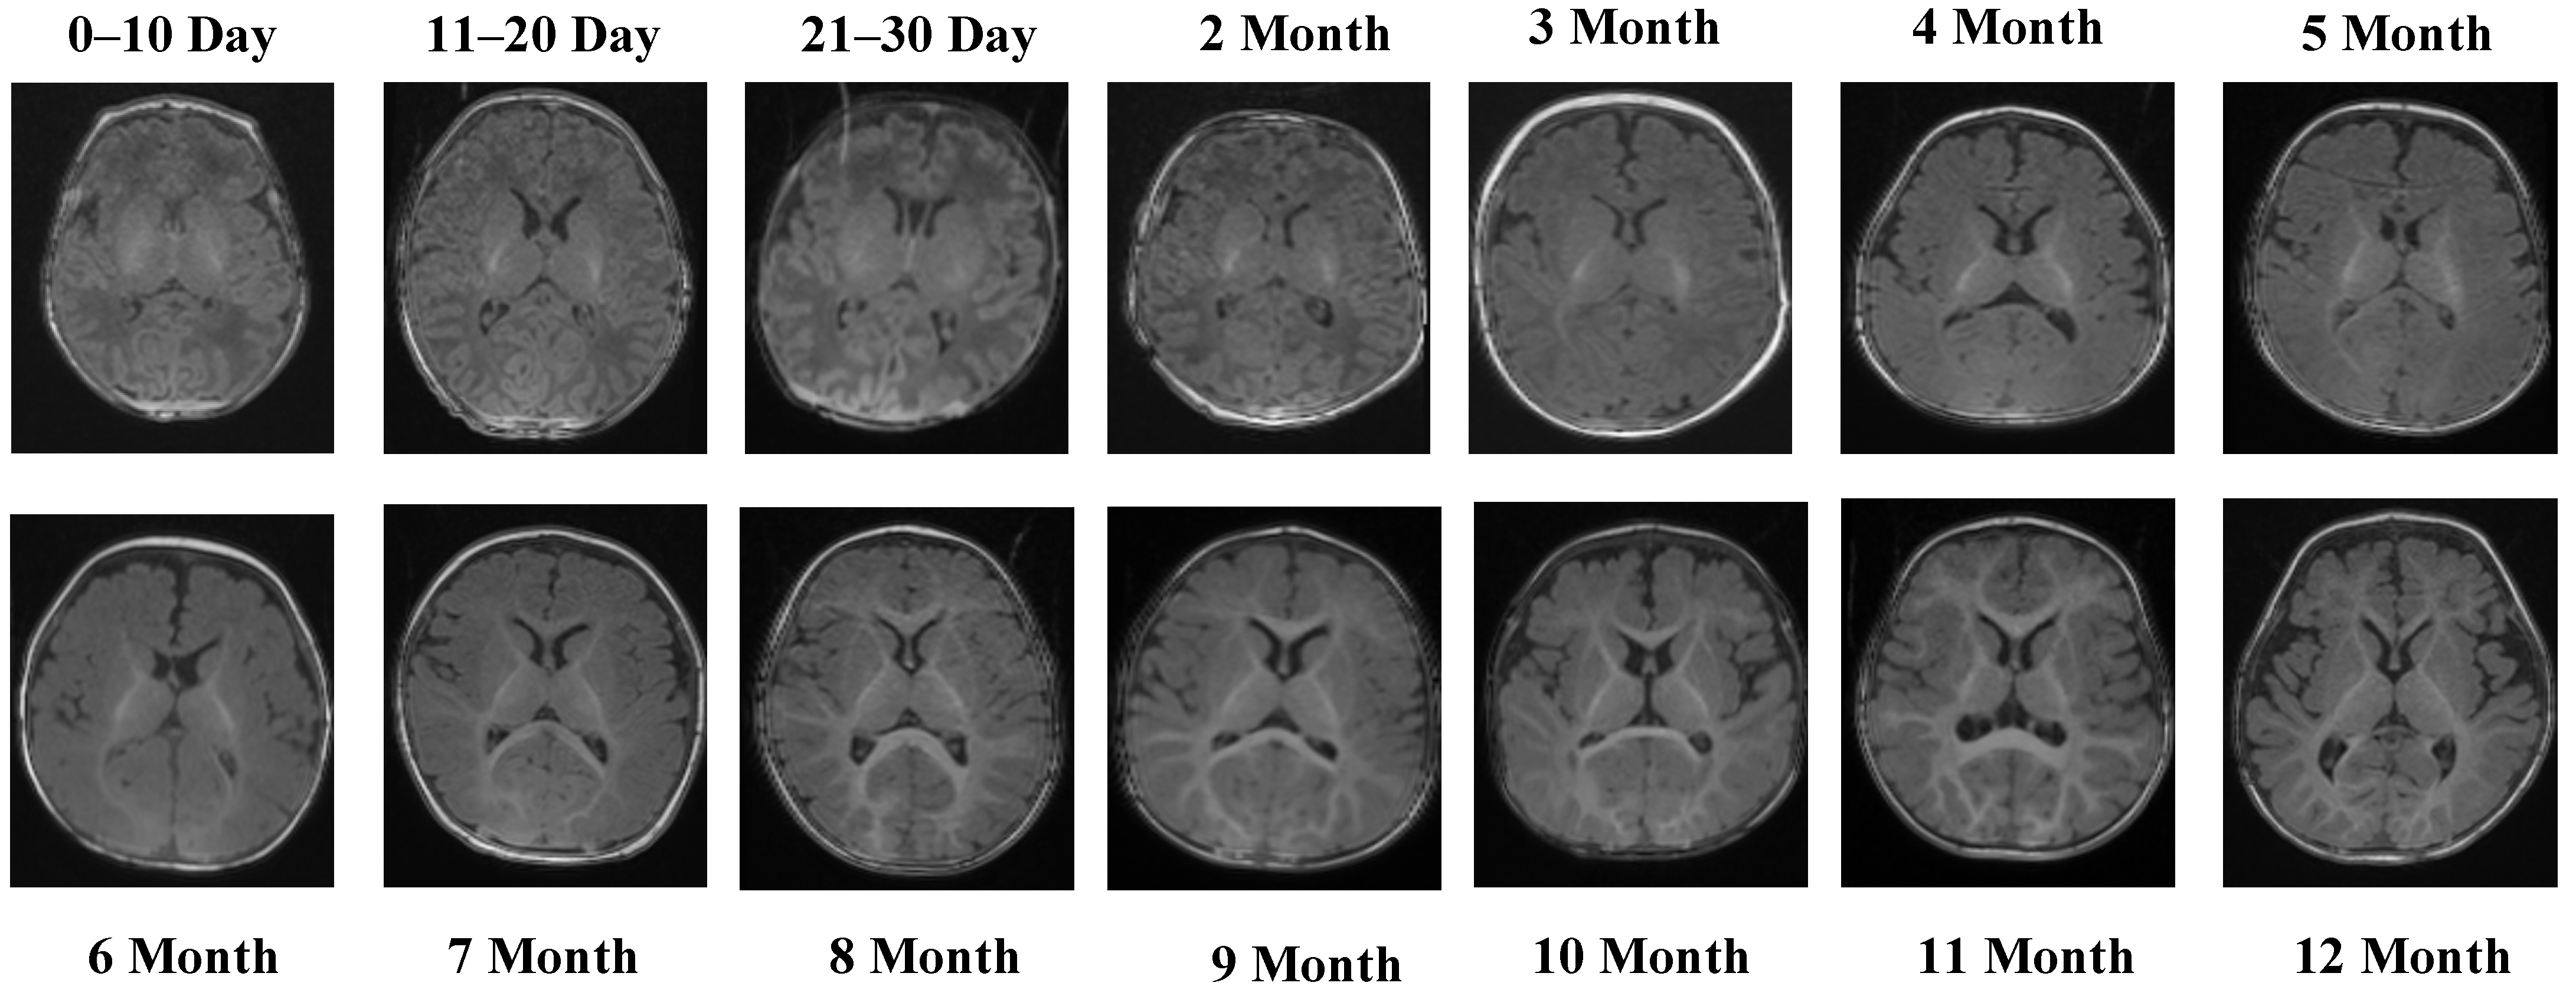

Representative MRI slices from the T1 Male sequence are shown in Figure 1, illustrating anatomical consistency across developmental intervals.

Figure 1.

MRI scans from the T1 Male sequence across different developmental groups.

Figure 1 illustrates representative MRI scans from the T1 Male sequence across different developmental groups, highlighting the anatomical consistency and quality of the data.

The T1 Male sequence contained 8154 images (6523 for training and 1631 for testing). The data are systematically organized from early neonatal stages (0–10, 11–20, and 21–30 days) to monthly intervals covering 2–12 months. This structured arrangement provides balanced coverage across both early infancy and later developmental stages. Examples of MRI slices from the T1 Female sequence are presented in Figure 2, demonstrating structural variation across neonatal and infant periods.